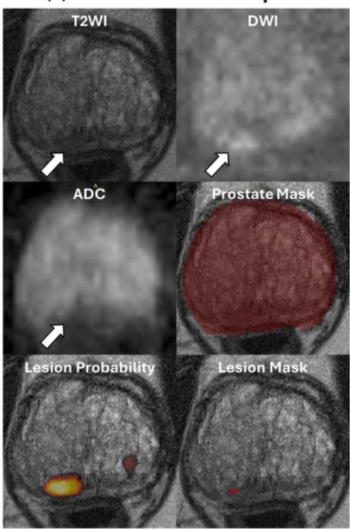

Demonstrating no significant difference with radiologist detection of clinically significant prostate cancer (csPCa), a biparametric MRI-based AI model provided an 88.4 percent sensitivity rate in a recent study.